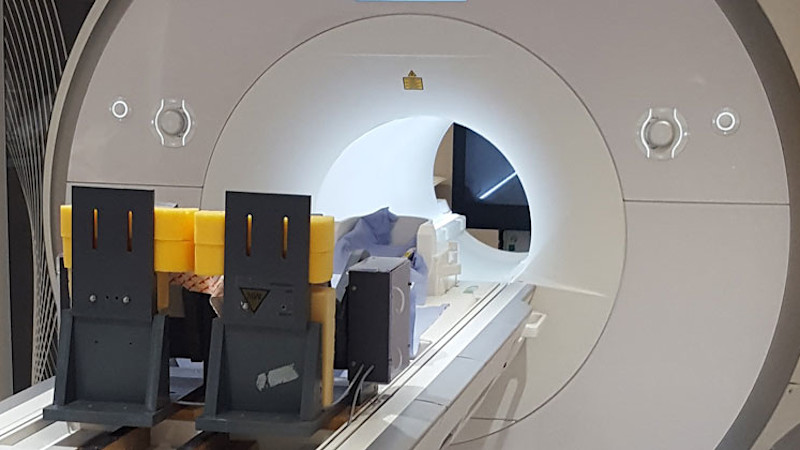

- Al-Yahya, E., P. Esser, B. D. Weedon, S. Joshi, Y. C. Liu, D. N. Springett, P. Salvan, A. Meaney, J. Collett, M. Inacio, A. Delextrat, S. Kemp, T. Ward, H. Izadi, H. Johansen-Berg, H. Ayaz and H. Dawes (2023). "Motor learning in developmental coordination disorder: behavioral and neuroimaging study." Front Neurosci 17: 1187790.

Joshi, S., B. D. Weedon, P. Esser, Y. C. Liu, D. N. Springett, A. Meaney, M. Inacio, A. Delextrat, S. Kemp, T. Ward, H. Izadi, H. Dawes and H. Ayaz (2022). "Neuroergonomic assessment of developmental coordination disorder." Sci Rep 12(1): 10239.